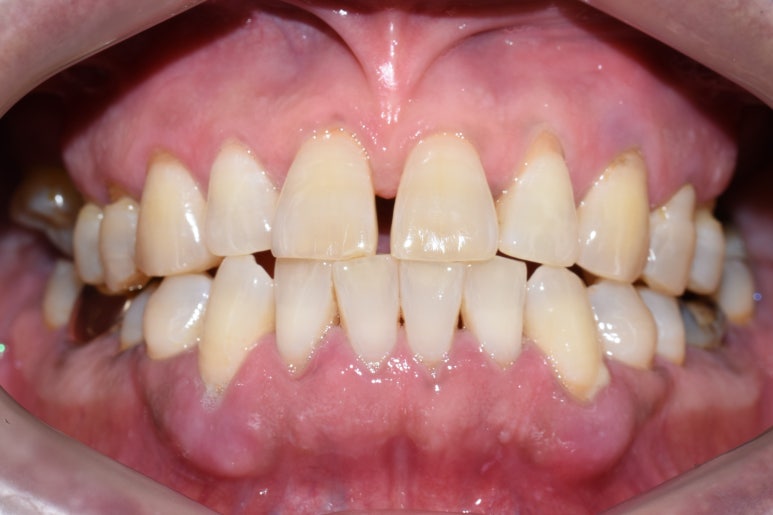

↑치료후에는 큰 어금니쪽 치아들을 윗니어금니 임플란트, 아랫니는 크라운 등으로 회복시켜

양쪽으로 잘 씹을 수 있게 되었습니다.